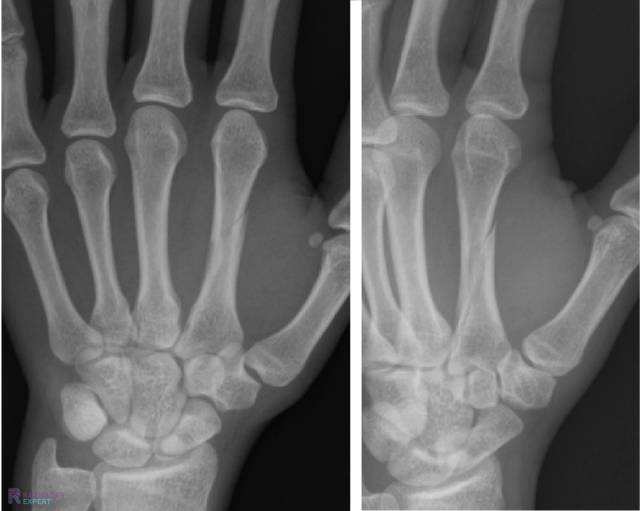

Figuur 1. Laterale en anterior-posterior opname van de linker onderarm/pols. Een kind (9 jaar oud) met distale radiusschacht & ulnaschacht fractuur. Beide tonen een dorso-ulnaire dislocatie over circa een schachtbreedte.